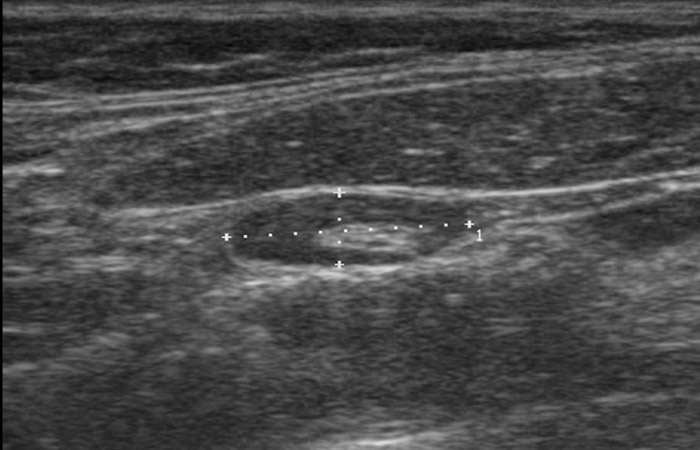

Με το υπερηχογράφημα, ο θυρεοειδής αδένας ελέγχεται για τις διαστάσεις του, την ομοιογένεια ή μη του παρεγχύματος, την παρουσία όζων καθώς και την αγγείωσή του.

Επίσης συμβάλει στην ανάδειξη τυχόν παθολογίας και στους παραθυρεοειδείς αδένες (παρουσία αδενωμάτων).

Με το υπερηχογράφημα τραχήλου πέρα από τον έλεγχο της ηχομορφολογίας των λεμφαδένων της περιοχής, απεικονίζονται και πιθανές άλλες αλλοιώσεις με την ίδια εντόπιση (π.χ. κύστη θυρεογλωσσικού πόρου, βραγχιακή κύστη).